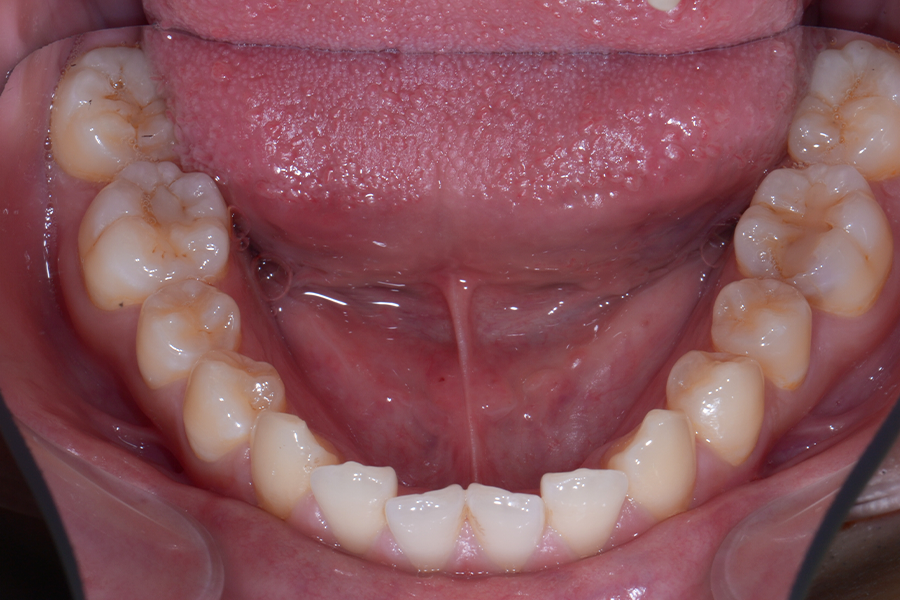

• 治療後